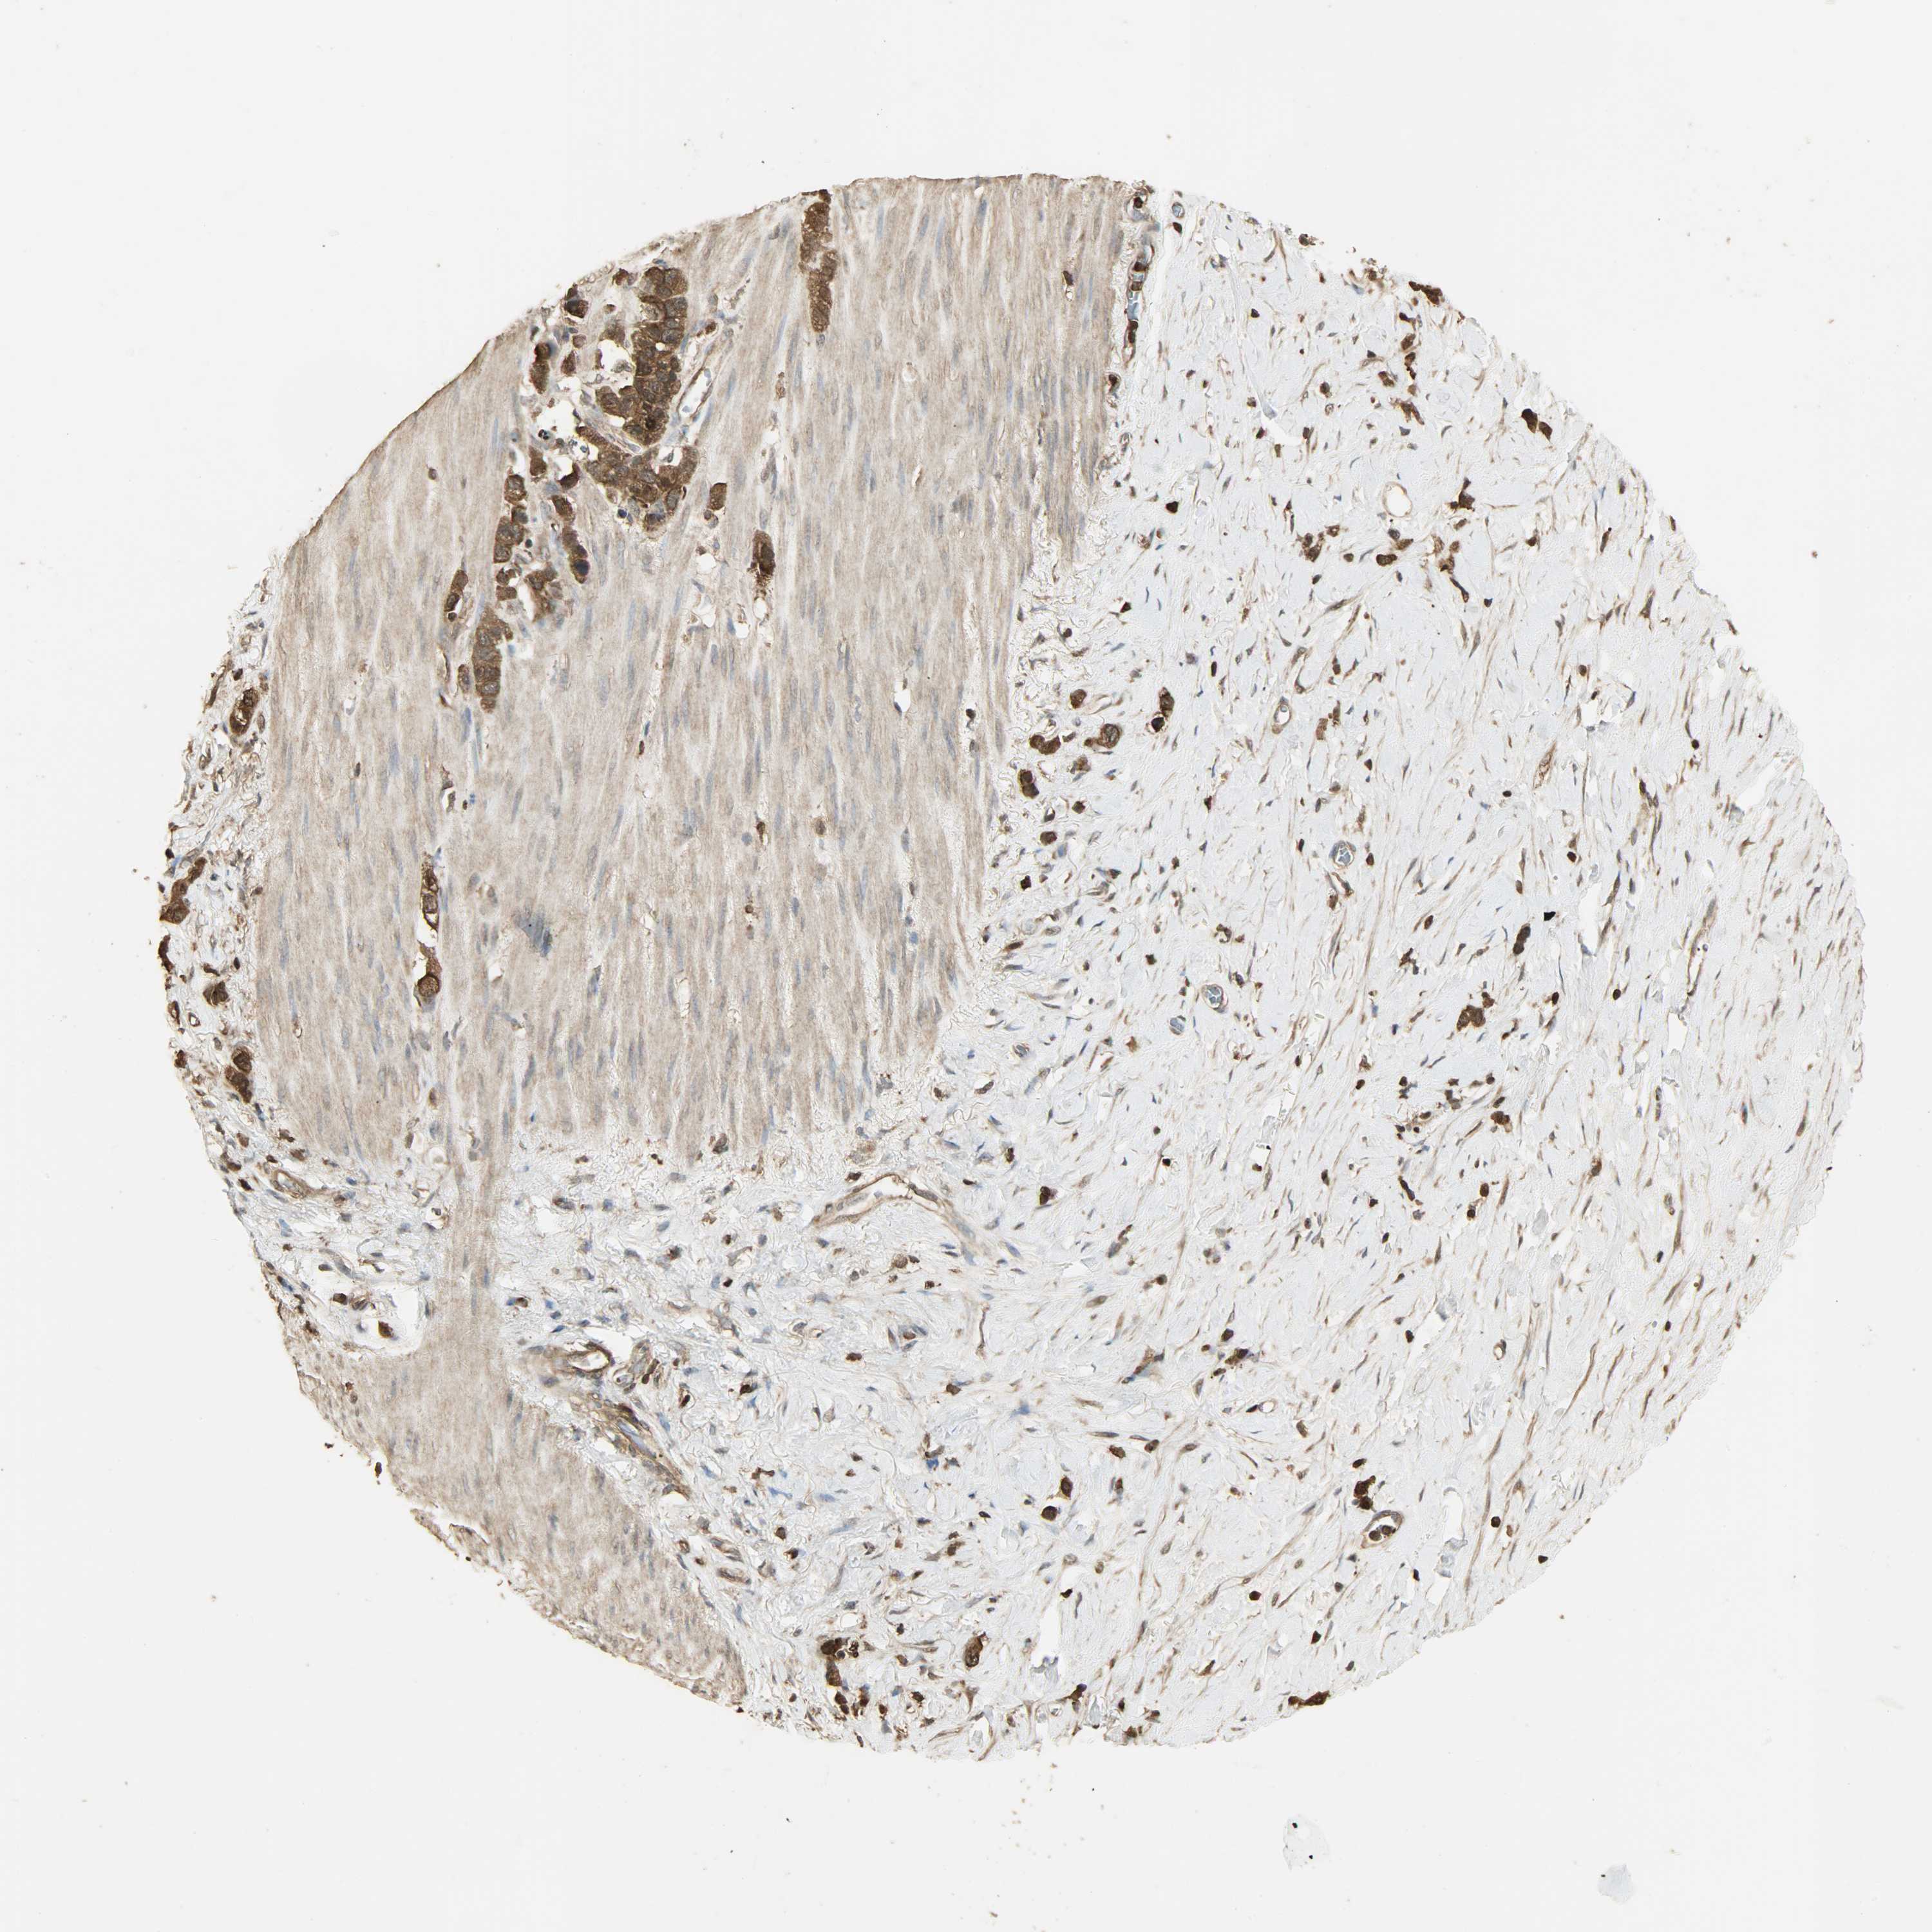

STOMACH CANCER - Protein expressioni

A mouse-over function shows sample information and annotation data. Click on an image to view it in a full screen mode. Samples can be filtered based on level of antibody staining by selecting one or several of the following categories: high, medium, low and not detected. The assay and annotation is described here.

Note that samples used for immunohistochemistry by the Human Protein Atlas do not correspond to samples in the TCGA dataset.

Antibody stainingi

Antibody staining in the annotated cell types in the current human tissue is reported as not detected, low, medium, or high, based on conventional immunohistochemistry profiling in selected tissues. This score is based on the combination of the staining intensity and fraction of stained cells.

Each image is clickable and will lead to virtual microscopy that enables deeper exploration of all samples and also displays staining intensity scores, fraction scores and subcellular localization as well as patient and tissue information for each sample.

Antibody CAB005065

Staining

High

Medium

Low

Not detected

Intensity

Strong

Moderate

Weak

Negative

Quantity

>75%

75%-25%

<25%

None

Location

Nuclear

Cytoplasmic/membranous

Cytoplasmic/membranous,nuclear

Adenocarcinoma, NOS

Adenocarcinoma, High grade